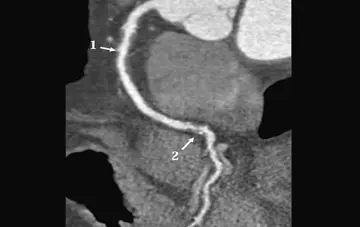

سی‌تی اسکن بر مبنای شمارش فوتون

سی‌تی‌اسکن PC چند محدودیت تکنولوژی فعلی سی‌تی را برطرف می‌کند. اگر چه فن‌آوری به کار گرفته شده در دتکتورهای آن جدید نیست ولی در حوزۀ سی‌تی پدیده‌ای نوین می‌باشد.